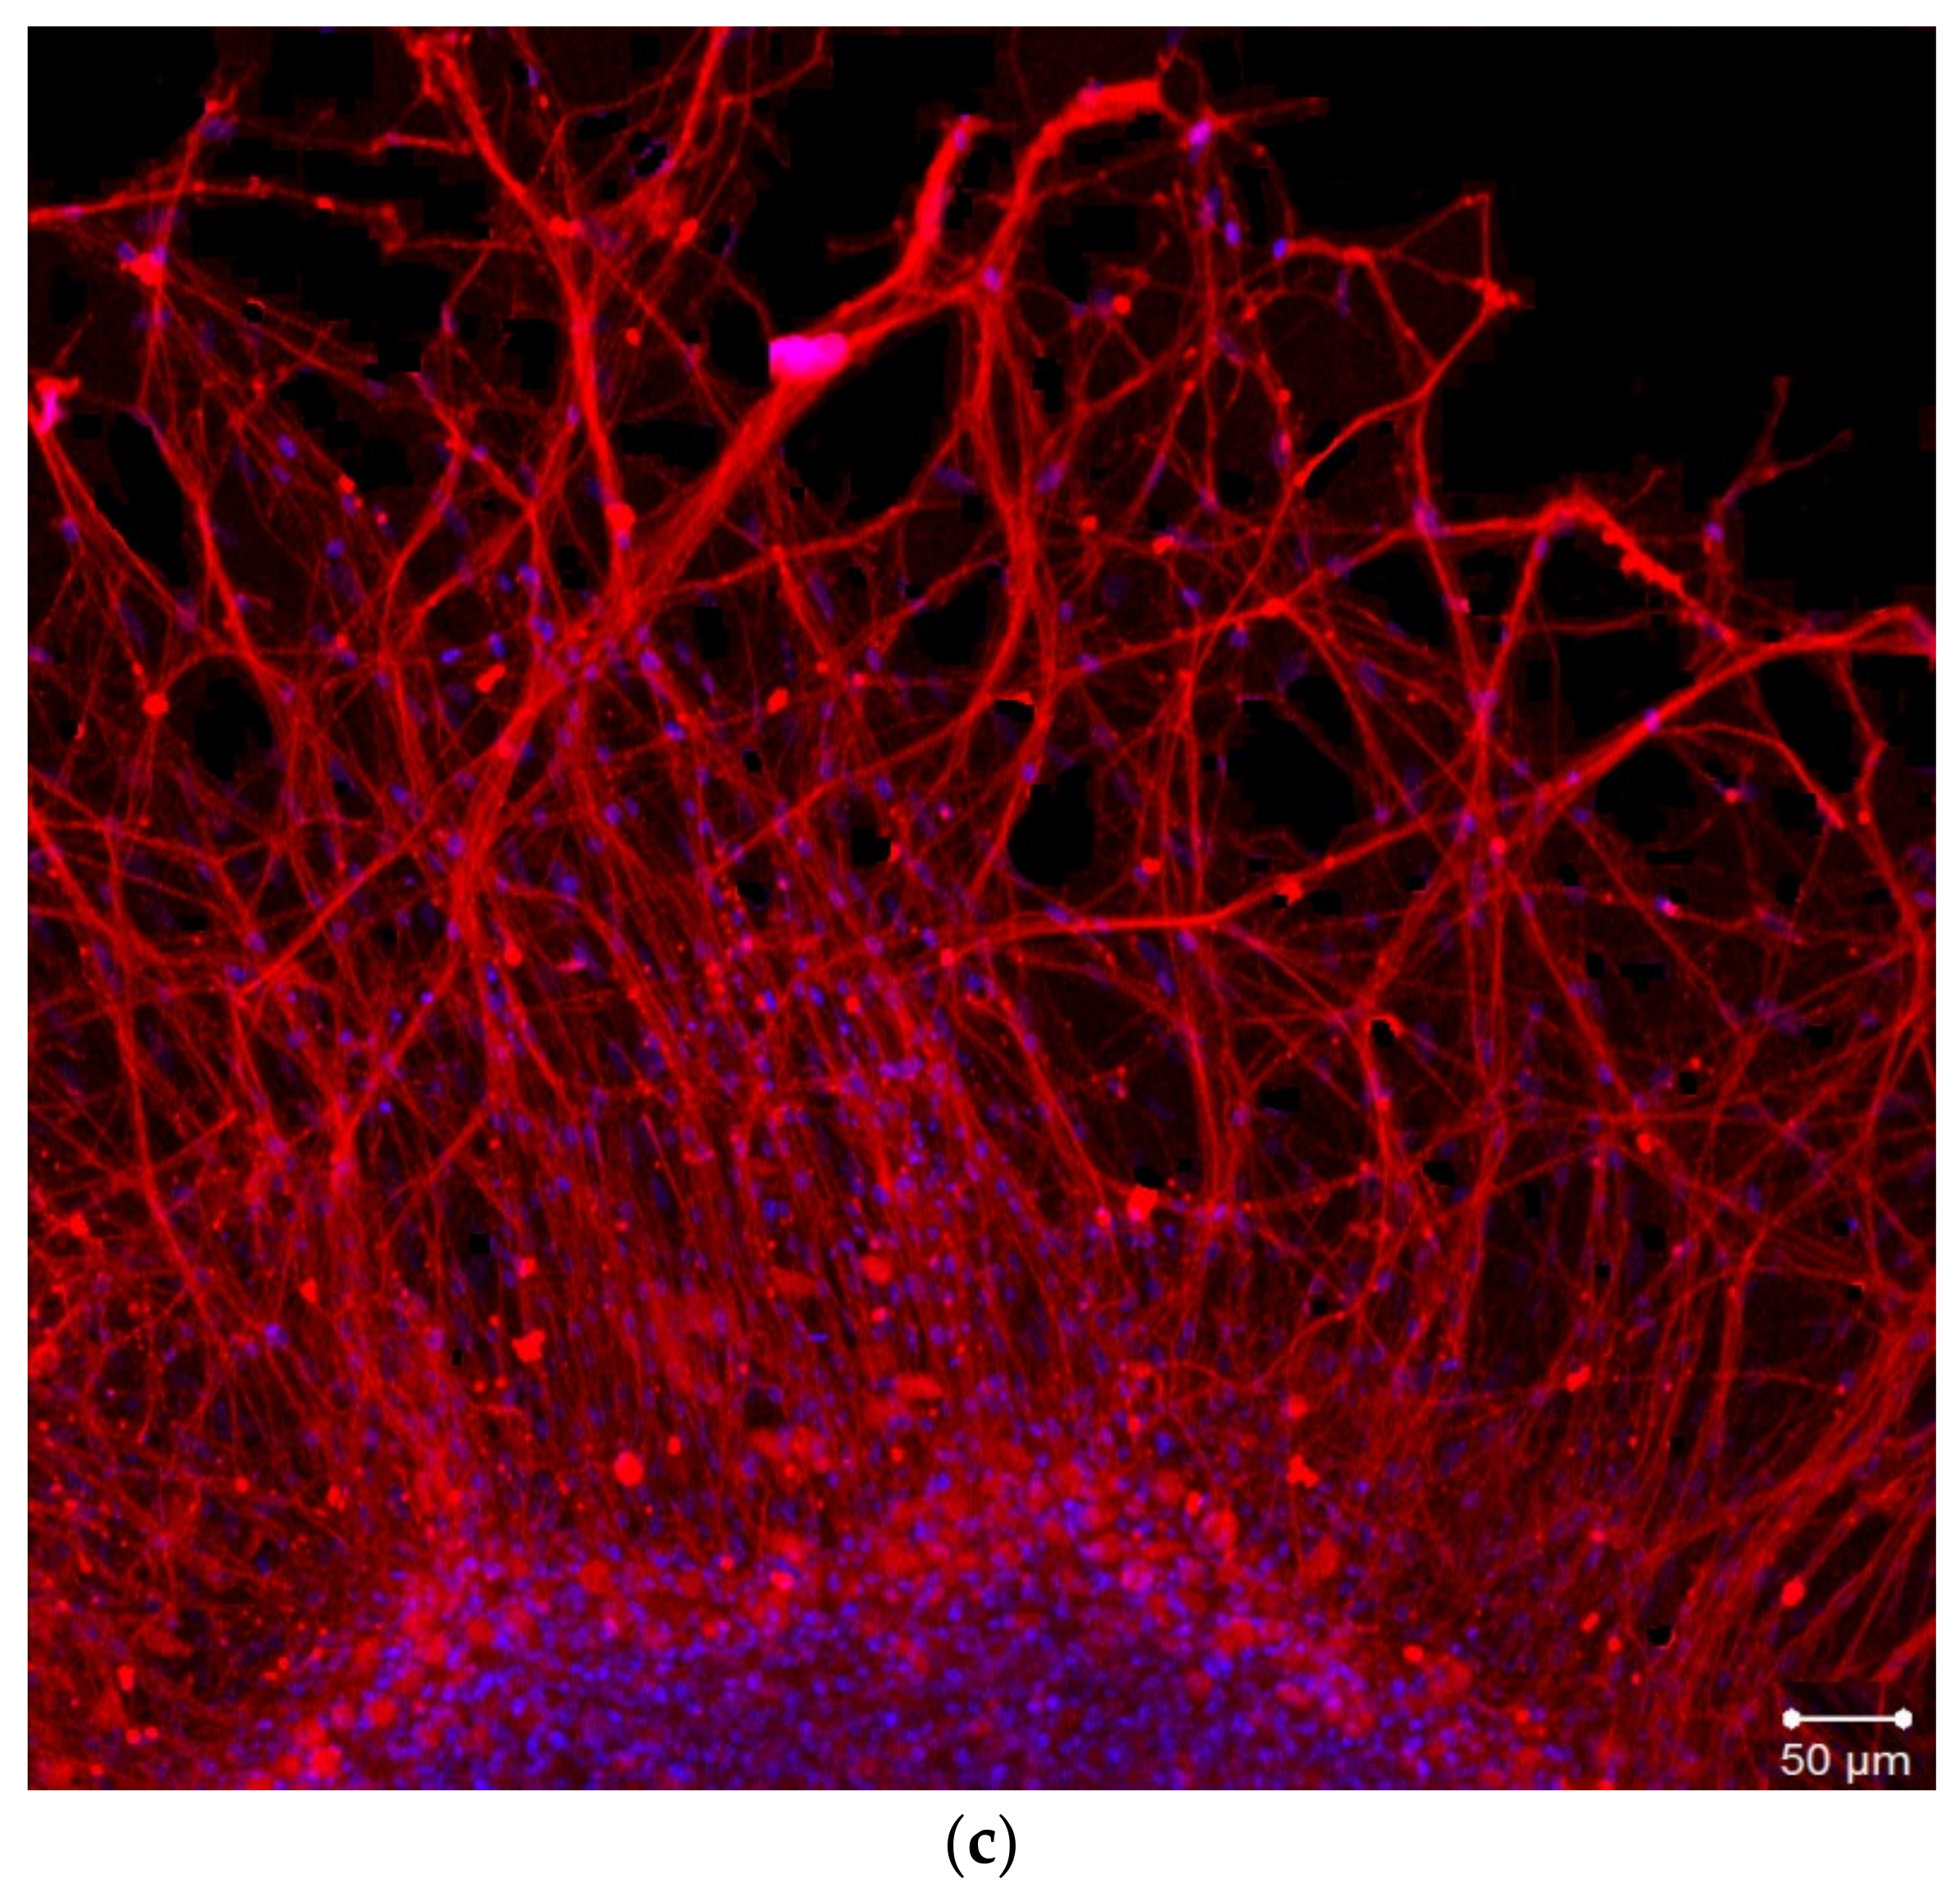

2.2. Organotypic Tissue Culture

4.3. Organotypic Nerve Tissue Culture Method

4.4. Immunostaining